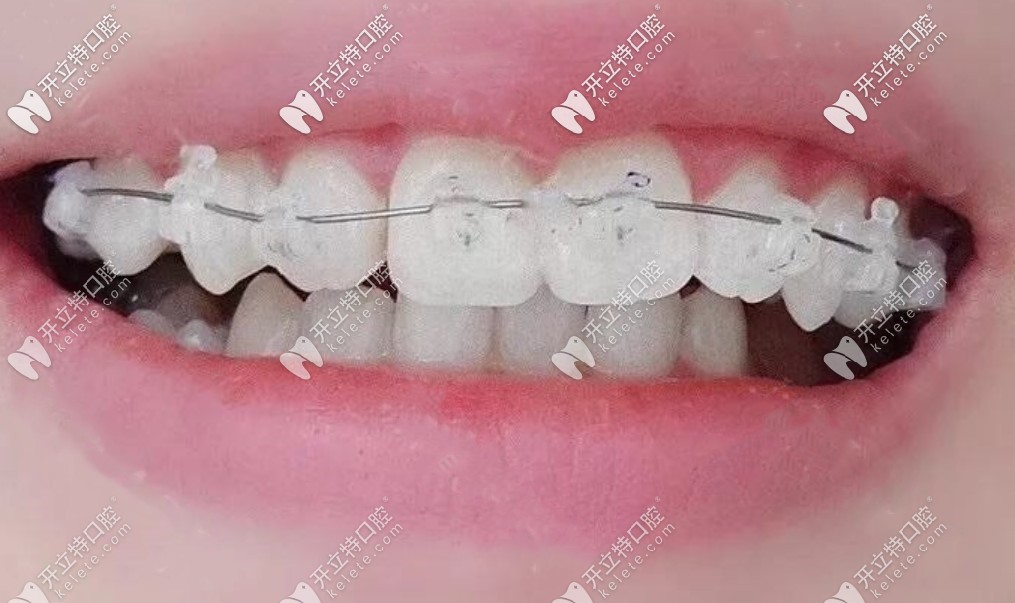

我戴上陶瓷自鎖托槽效果圖▼

我戴上陶瓷自鎖托槽效果圖